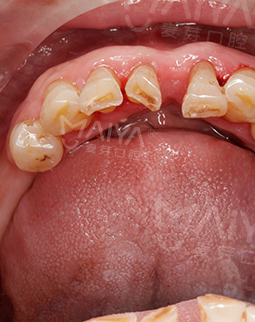

过去的困扰

以前的口腔保护意识差,牙齿逐渐下岗。做了活动假牙,异物感非常重,也给我的生活带来很多烦恼。为了重新拥有好牙口,了解了很多补牙的知识,自己都快成口腔专家了,要种牙就要找到能给我满意的修复意见的医生!